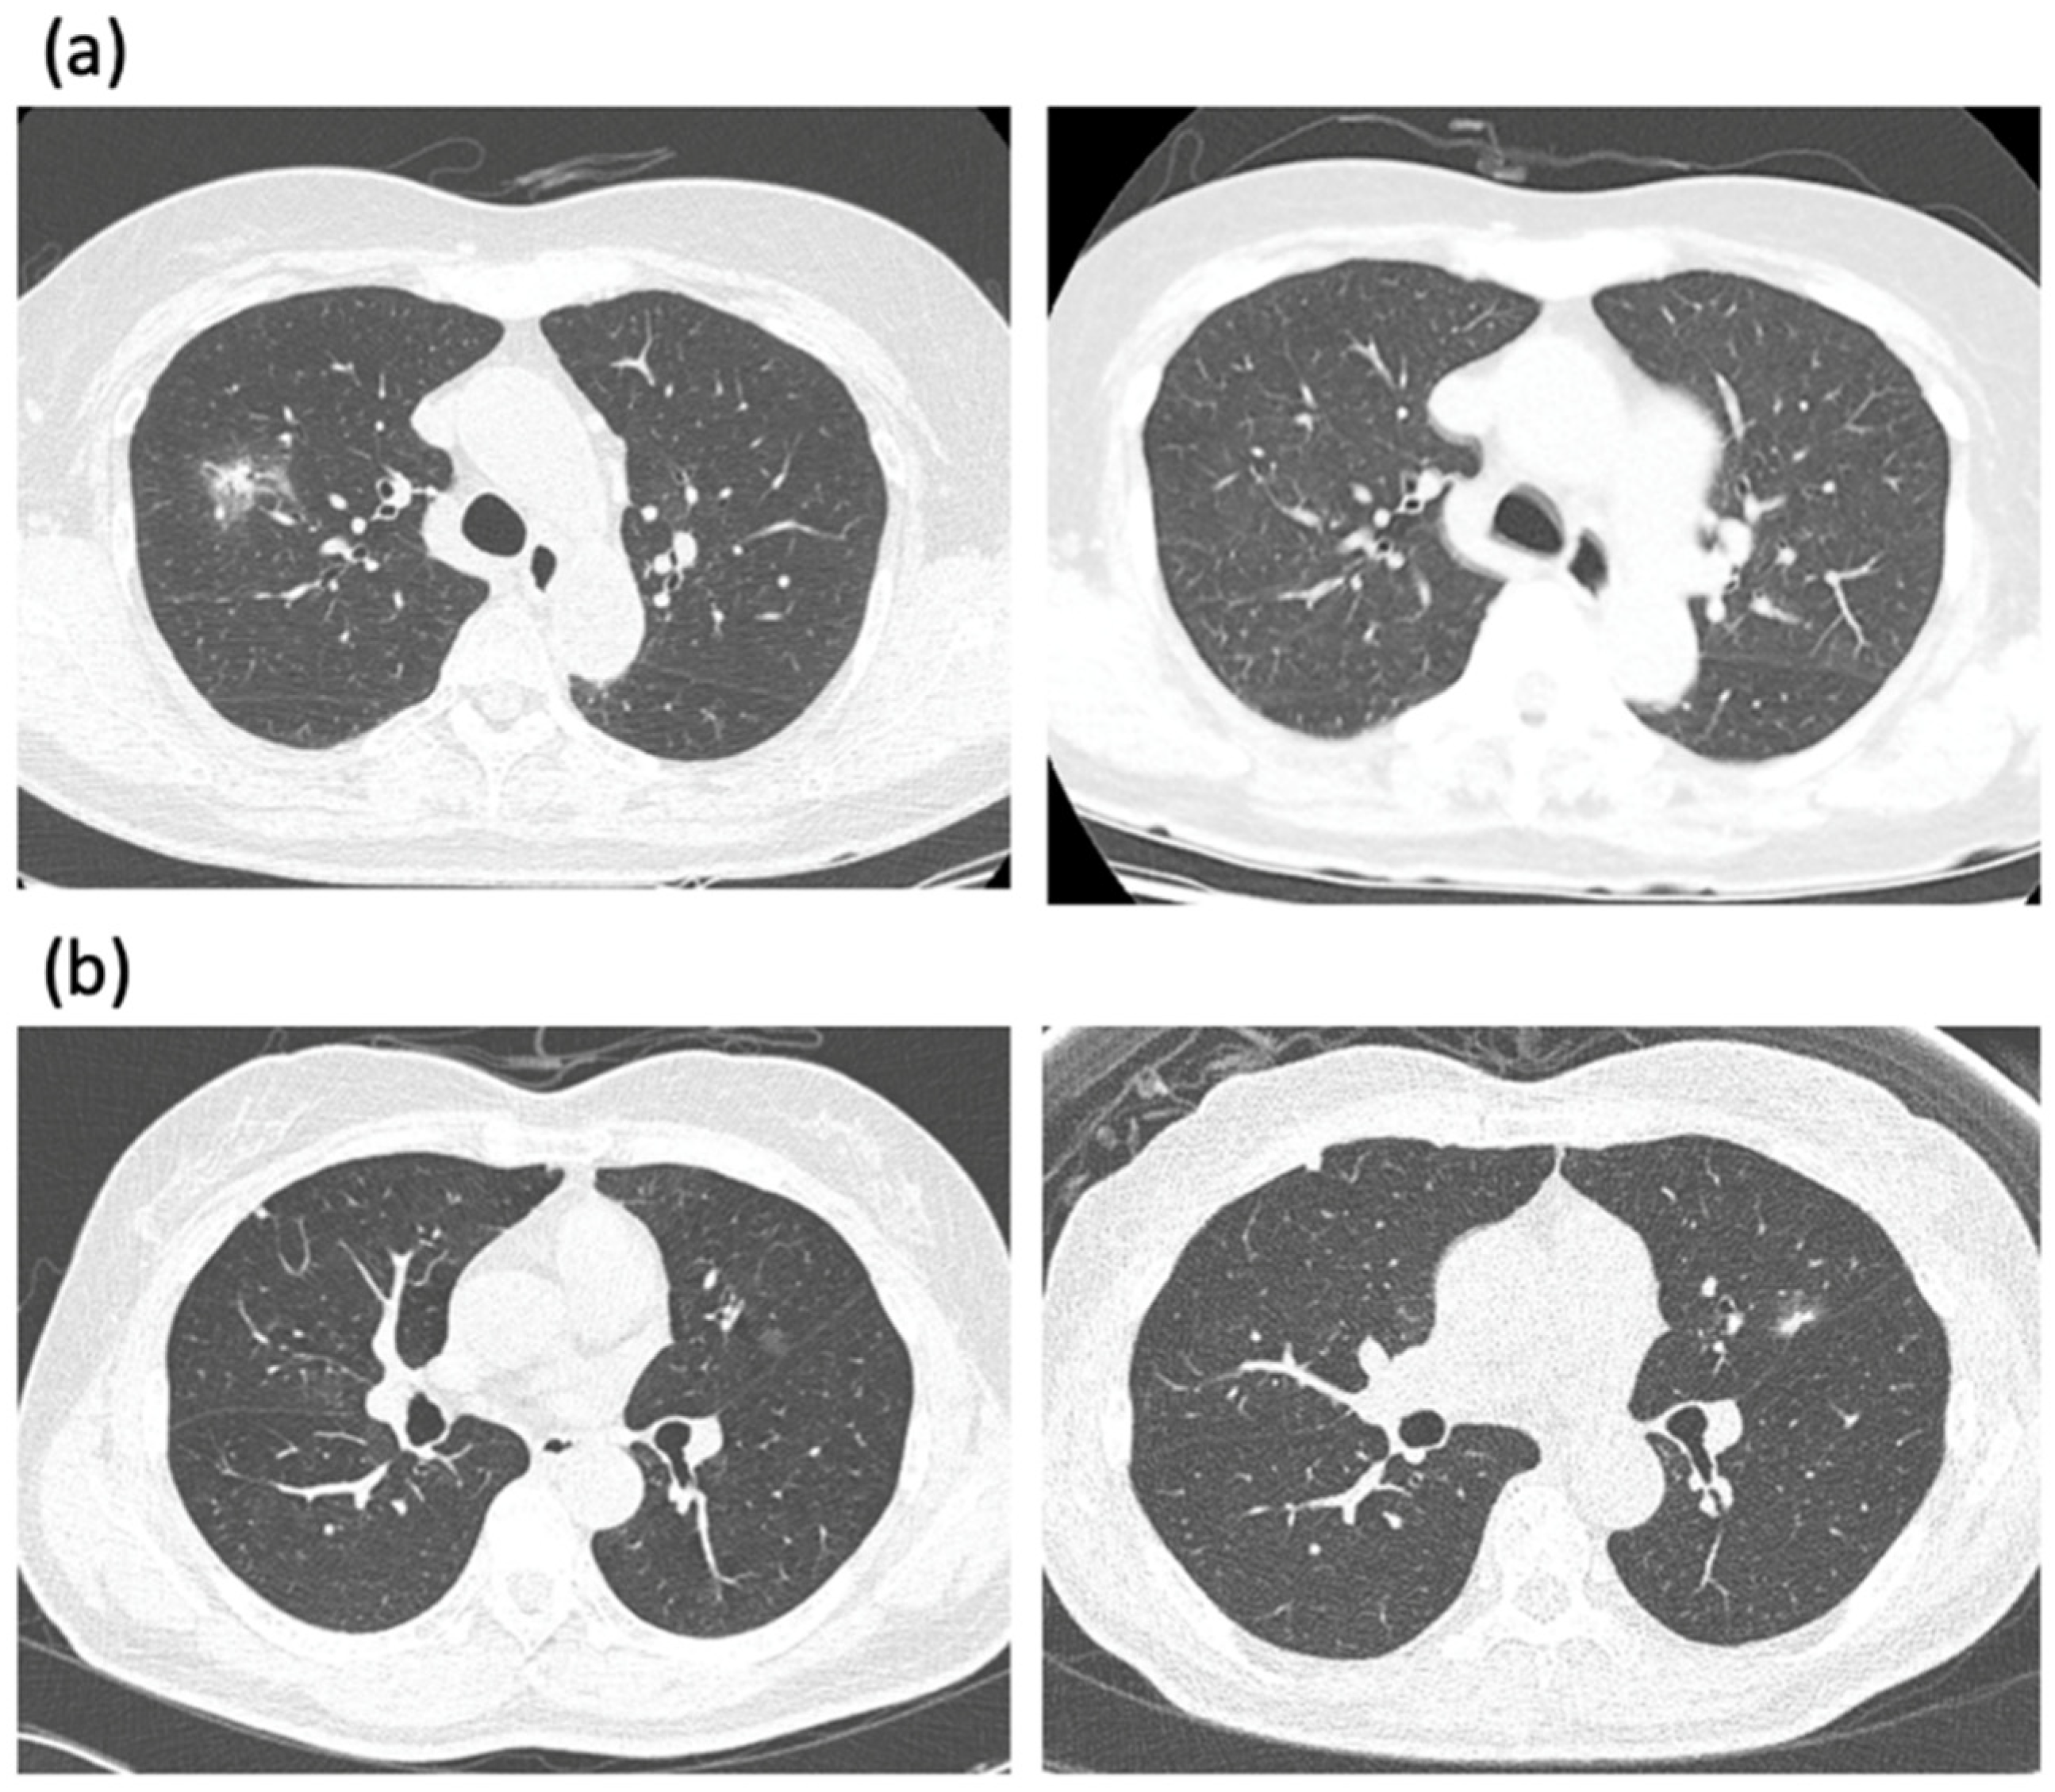

2. Predicting Malignant GGN

3. The First Dilemma: When to Intervene?